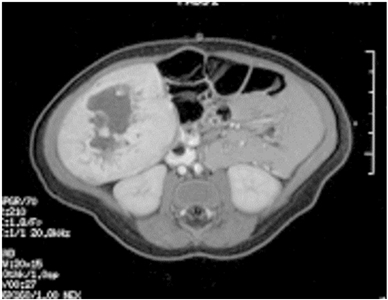

Los hemangiomas se suelen diagnosticar por los antecedentes y el aspecto clínico. Pocas veces se necesita una biopsia y solo se realiza si el aspecto, los antecedentes y la presentación clínica inicial son atípicos. Por lo general, no se necesitan pruebas con imágenes, pero una ecografía diagnóstica es útil cuando hay una lesión más profunda sin un componente cutáneo que exhibe una lesión de flujo alto hipoecogénica bien circunscrita con una característica típica de onda Doppler.[37] Además, los lactantes con 5 o más hemangiomas cutáneos se deben someter a una ecografía de hígado para descartar la presencia de un hemangioma hepático.[38]